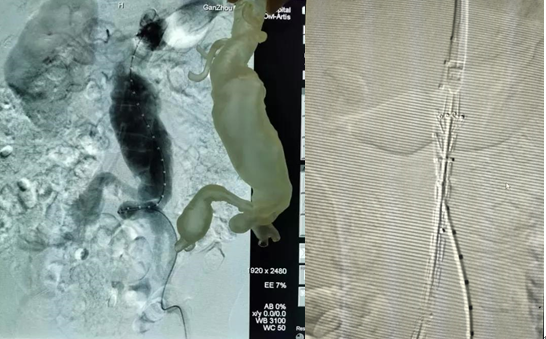

1、 3D打印腹主動(dòng)脈瘤及分支血管,充分了解血管解剖結(jié)構(gòu)。

2、 左右髂總動(dòng)脈血管迂曲,左右腎動(dòng)脈位置差異較大。

3、 3D打印血管為手術(shù)方案的制定和血管支架的選擇提供參考。

1.根據(jù)3D打印血管制定的手術(shù)方案,腹主動(dòng)脈血管造影,提示動(dòng)脈瘤位置及各血管分支情況。